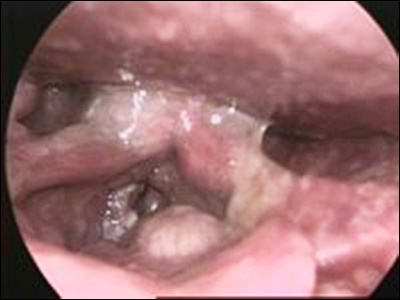

후두암 진단: 기대할 수 있는 절차

후두암 의심 시, 정확한 진단을 위해 다양한 절차가 있습니다. 주요 진단 방법으로는 후두조직 생검, 엑스레이, 초음파, 컴퓨터 단층 촬영(CT), 자기공명영상(MRI), PET-CT 등이 있습니다. 이러한 절차들을 통해 후두암의 위치, 크기 및 확산 여부를 확인할 수 있으며, 정확한 진단과 치료 계획을 세울 수 있습니다.